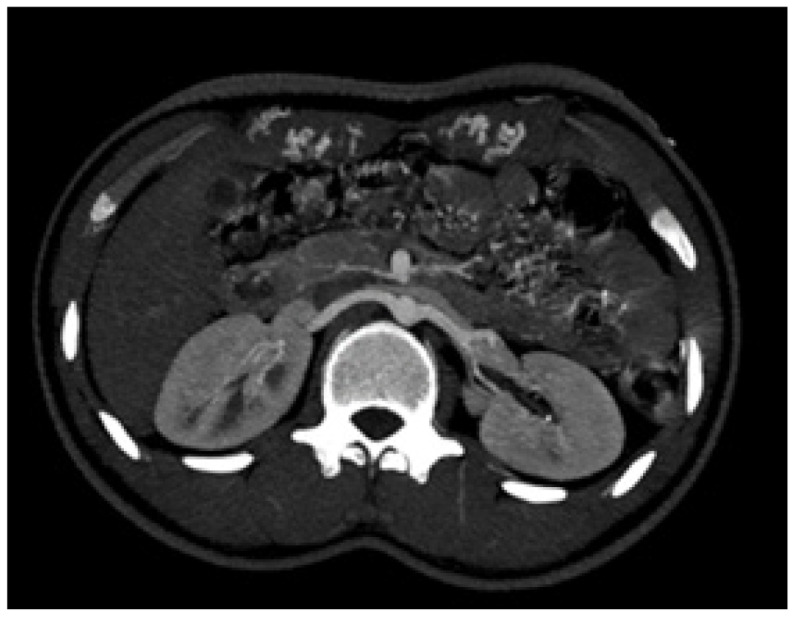

Case presentation: A 20-year-old patient was admitted to our hospital as he complained of headache and palpitations since one week. On examination, the blood pressure in his right upper limb was 180/100 mmHg. The volume of the femoral and the dorsalis pedis pulses was found to be reduced bilaterally. The patient was started on antihypertensive medication labetalol 10 mg injection intravenously immediately. After clinical suspicion and a series of investigations, the patient was diagnosed with severe CoA, distal to the origin of the left subclavian artery via computed tomography (CT) aortogram. The patient was managed by coarctoplasty with stenting.